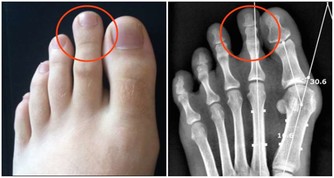

多發性骨髓瘤這種疾病多發於老年人,並且年齡越大發病率越高,是成正比的,這種疾病最初的表現症狀也是腰痛,但是除了腰痛之外,這個疾病還會侵犯身體其他的骨頭,也就會導致身體其他部位的疼痛,多發性骨髓瘤會侵犯人的運動系統,最嚴重的後果是導致骨折,老年人的骨折往往都是致命的,因為老年人骨折後的臥床會帶來很多的並發症。

多發性骨髓瘤這種疾病多侵犯人的骨頭、骨髓,所以常常腰痛伴有周身疼痛,並且多發性骨髓瘤這種疾病也是一種惡性腫瘤,如果家裡的老人長時間的腰痛就要帶著去醫院檢查一下,排查一下多發性骨髓瘤。